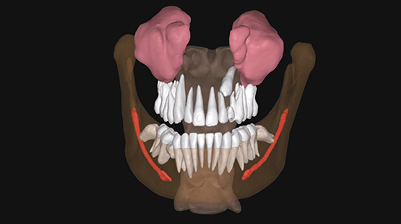

Удобное ортодонтическое планирование и консультации

5D предлагает интуитивно понятную 3D-визуализацию ретинированных и сверхкомплектных зубов, улучшая общение и обеспечивая понятные объяснения пациенту.